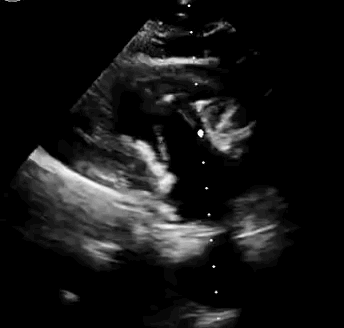

本次臨床前研究經(jīng)右側(cè)頸靜脈置入LuX-Valve Plus輸送系統(tǒng)可調(diào)彎鞘管,在DSA及超聲引導下將人工三尖瓣瓣膜植入到原有三尖瓣位置,利用獨特的錨定技術(shù)將人工瓣膜支架可靠固定在預定的位置。